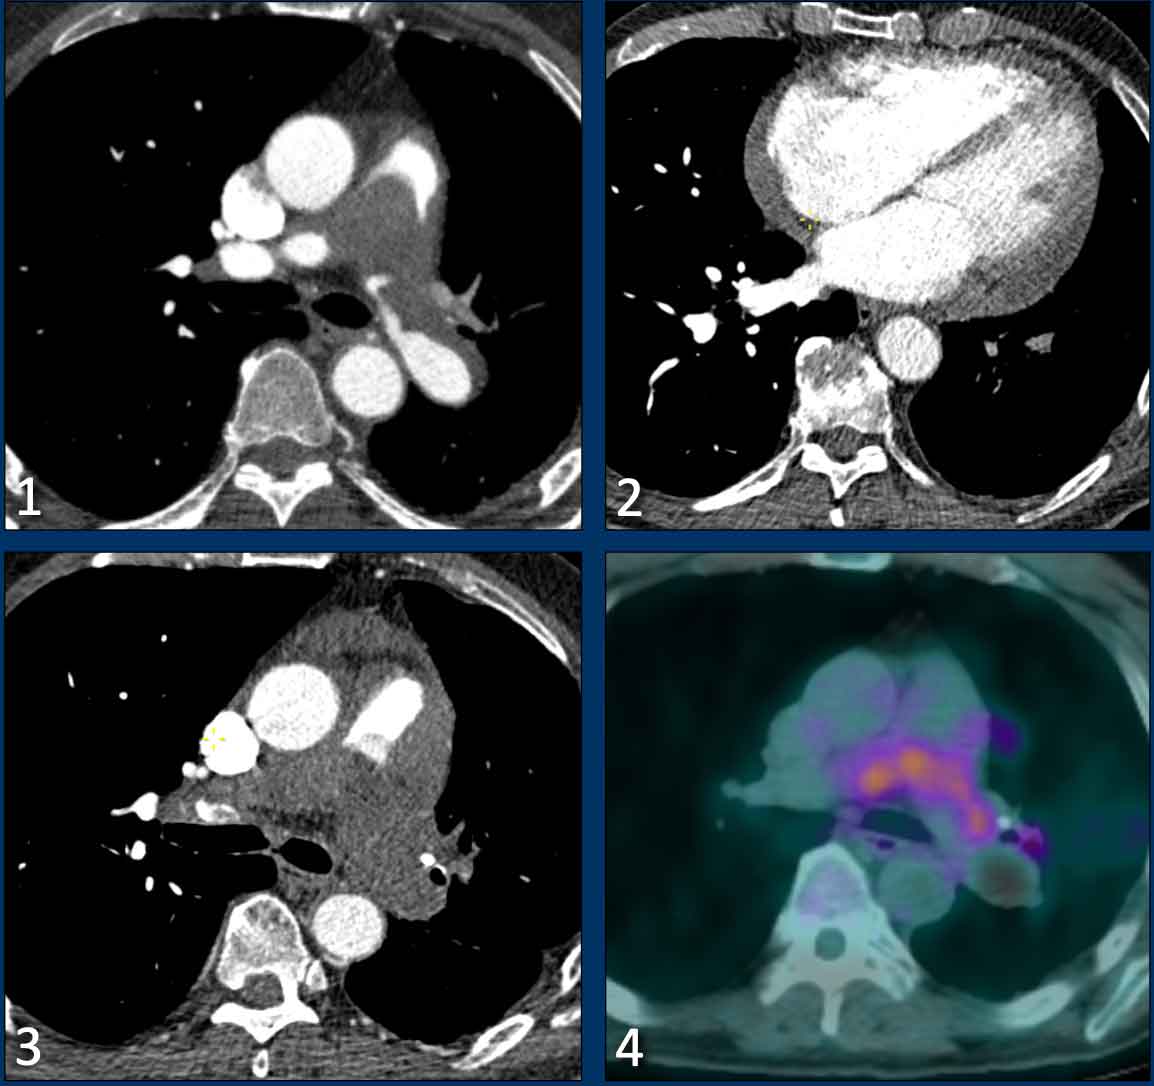

Cardiac remodelling in pulmonary emboli

Looking at remodelling of the right ventricle can help to differentiate between acute and chronic emboli.

Here we have two examples of patients with pulmonary emboli and cardiac remodelling.

Images

1. There is right ventricular dilatation with septal flattening, but no evidence of RV wall hypertrophy (black arrow), consistent with an acute increase in RV afterload.

This can be seen in patients with acute pulmonary embolism.

2. In contrast, in this patient there is dilatation of the right ventricle and atrium with interventricular septal flattening, accompanied by RV wall thickening (white arrow).

This suggests chronic pressure overload and is indicative of longstanding pulmonary hypertension.

This can be seen in patients with chronic thromboembolic pulmonary hypertension.